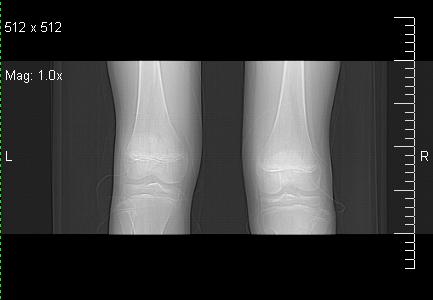

标题: CT19091:右胫骨近段骨性突出. [打印本页]

标题: CT19091:右胫骨近段骨性突出.

男,15岁,右胫骨近段软组织肿胀,下肢疼痛10左右.

右胫骨近端内侧骨性突起,皮质连续,骨质结构正常,首先考虑胫骨骨软骨瘤,随访观察。